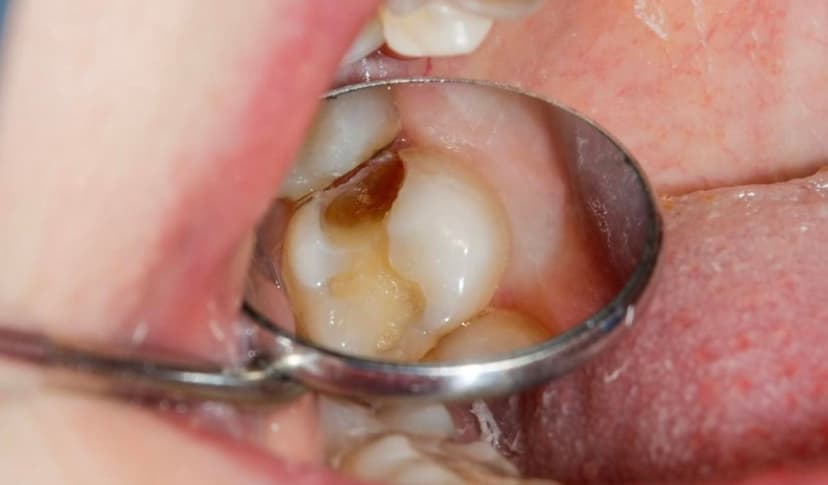

1.1 Thế nào là tình trạng răng sâu bị lồi thịt?

Răng sâu lồi thị là tình trạng trong đó vết sâu đã lan rộng đến gần thịt nướu. Điều này gây ra việc thịt nướu bị lồi ra. Khi răng bị sâu lồi thịt, nướu thường trở nên sưng đau và nhạy cảm. Đặc biệt là khi nướu tiếp xúc với thức ăn hoặc lạnh. Nếu không được điều trị, vi khuẩn trong vết sâu có thể lan rộng. Điều này gây ra viêm nhiễm nặng hơn. Thậm chí, sâu răng có thể gây ra đau và tổn thương cho các cấu trúc xung quanh răng.